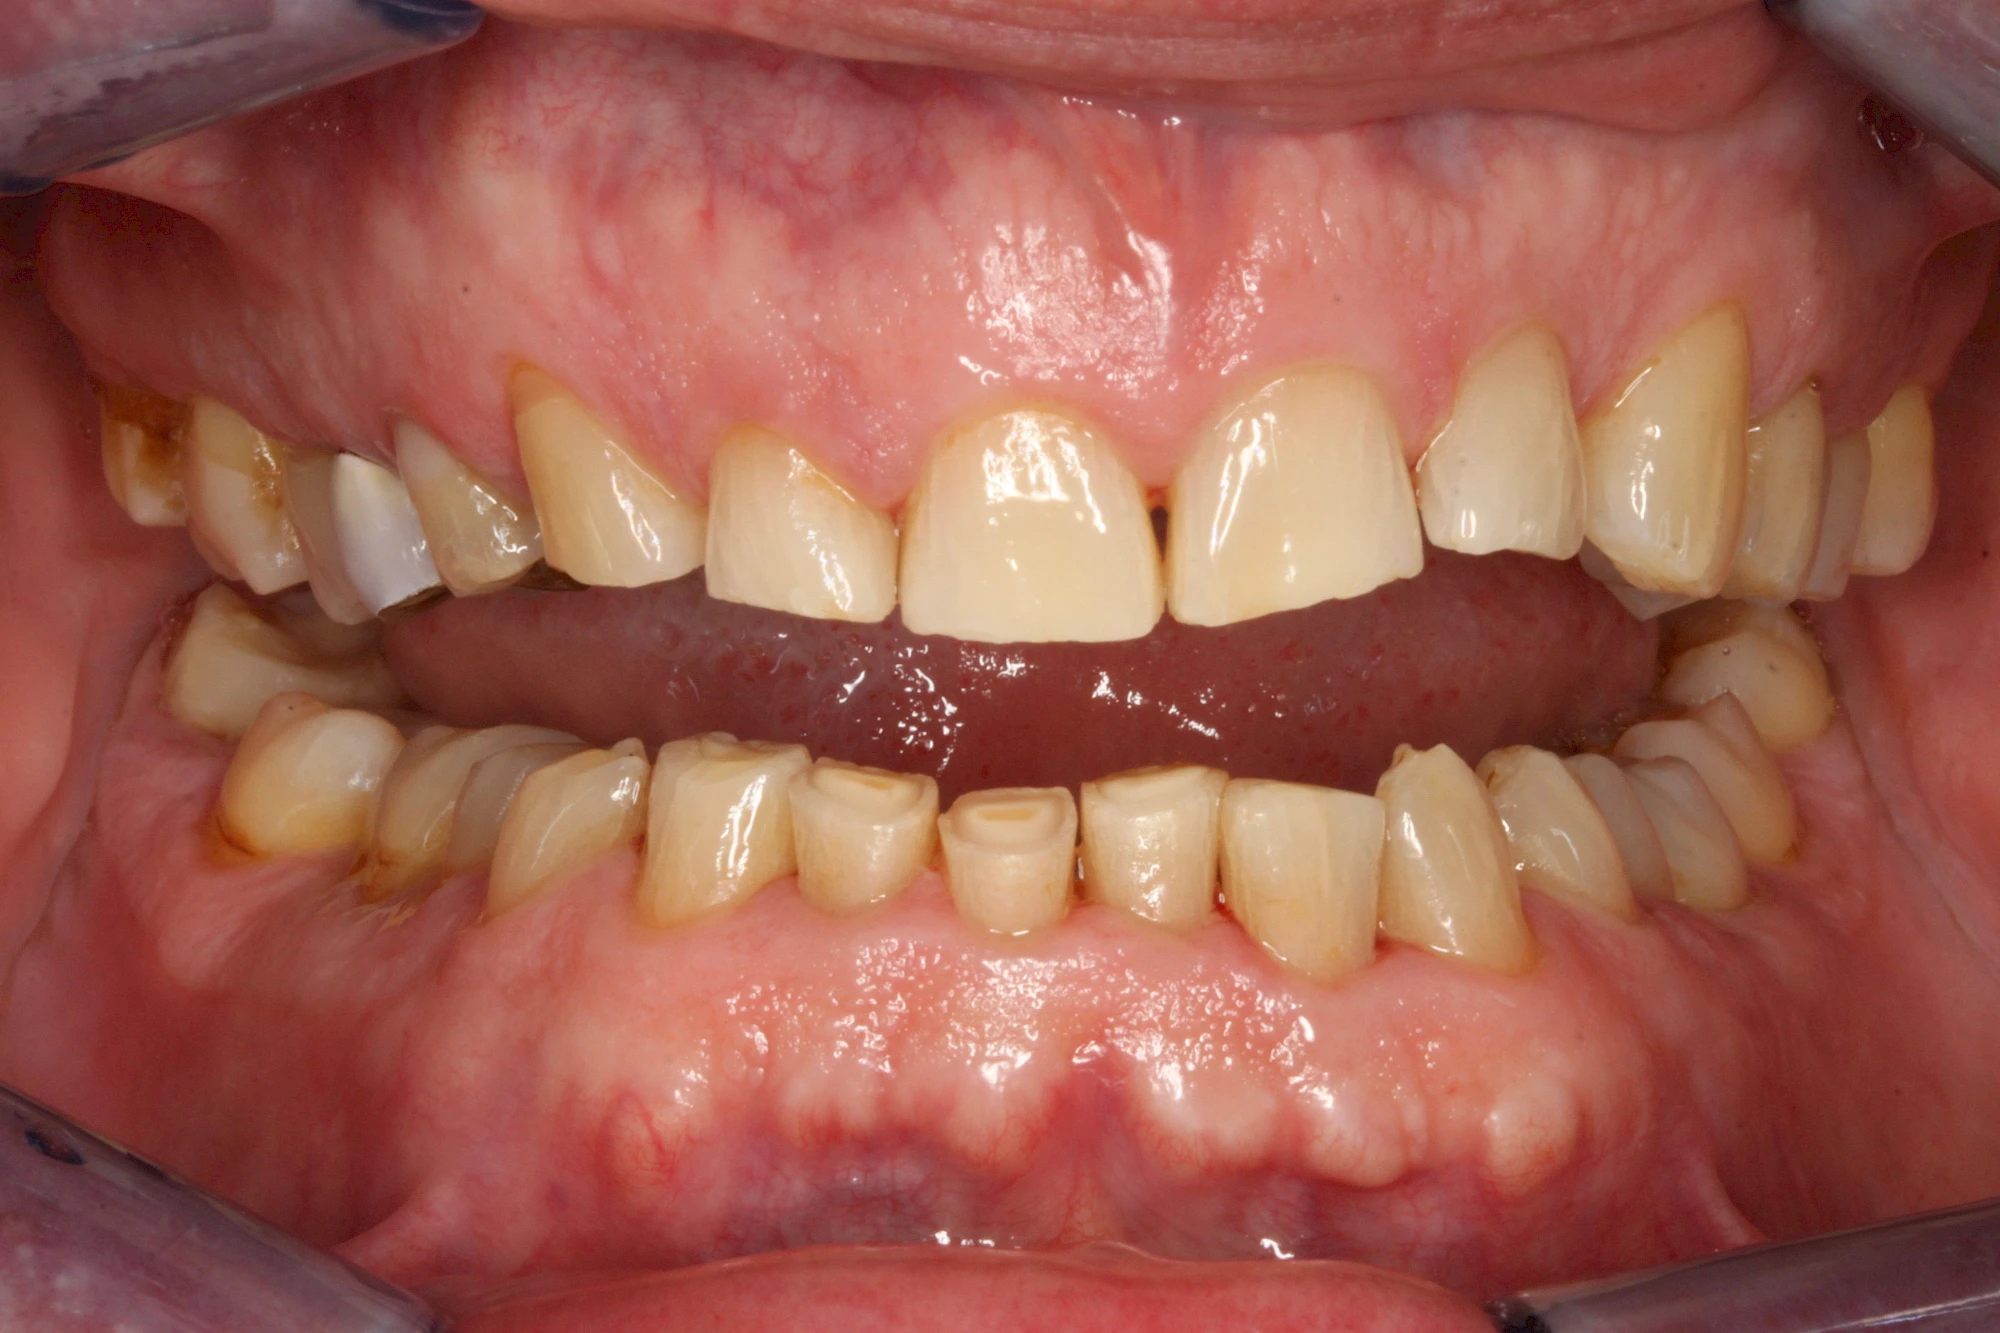

Über die Zeit können verschiedene Prozesse die Zahnhartsubstanzen aufzehren:

- Abnutzung durch Kauen (Abrasion) oder duch durch übermäßiges Knirschen bzw. Pressen (Attrition)

- Säurebedingte Auswaschung (Erosion)

- Knirschen bzw. Pressen und ungünstige Putztechnik (Druck): keilförmige Defekte

Die Zähne können dabei auf Reize (warm, kalt, süß, sauer) oder auch beim Zähneputzen empfindlich oder schmerzhaft sein. In allen diesen Fällen ist es sinnvoll, den Zahnarzt zu kontaktieren und das weitere Vorgehen abzustimmen.